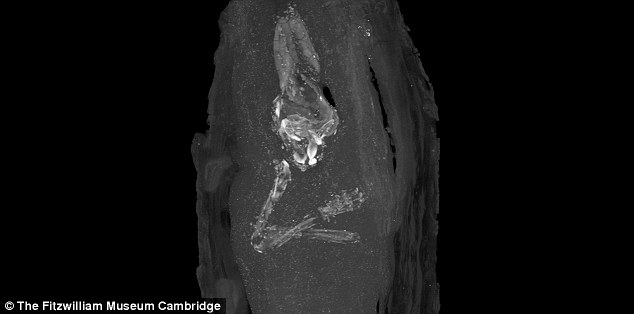

The world's youngest mummy has been found in a small Egyptian coffin at a British museum.

The foetus is believed to have been no older than 18 weeks of gestation when it was preserved during an ancient burial ritual.

The discovery reveals 'just how precious the unborn child was' to the Egyptians, and how they dealt with miscarriage, historians have said.

The discovery reveals 'just how precious the unborn child was' to the Egyptians, historians have said. Pictured is a micro CT scan image of the upper limbs and skull of foetus